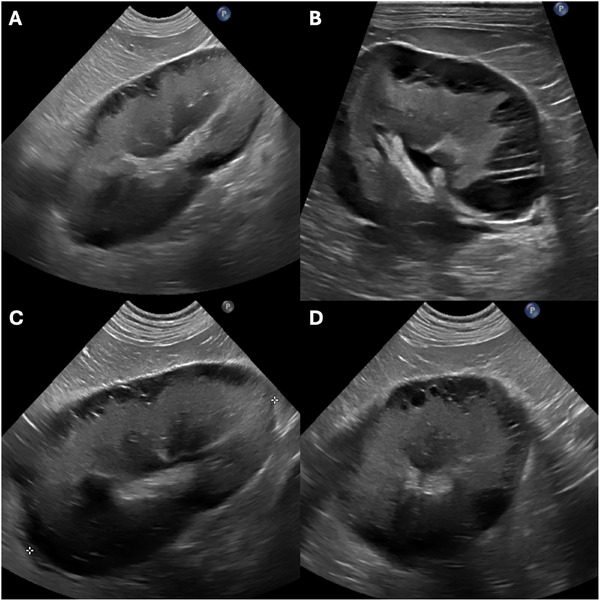

A 9-year-old male neutered Labrador Retriever was referred for azotemia and bilateral renomegaly. An abdominal ultrasound revealed severe bilateral renomegaly with septated subcapsular cystic anechoic lesions, consistent with renal lymphangiectasia. Despite conservative management, the patient died. Necropsy and histopathology confirmed dilated subcapsular vascular structures. Renal lymphangiectasia is a rare, benign dilation of renal lymphatics previously reported in human medicine. This case represents the first description of sonographic features of renal lymphangiectasia in a canine patient.

一只9岁的拉布拉多雄性绝育猎犬因氮血症和双侧肾肿大而被转诊。腹部超声显示严重双侧肾肿大伴囊下分离性囊性无回声病变,符合肾淋巴管扩张。尽管进行了保守治疗,患者还是死亡了。尸检和组织病理学证实包膜下血管结构扩张。肾淋巴管扩张是一种罕见的,良性扩张的肾淋巴管先前报道在人类医学。本病例首次描述犬患者肾淋巴管扩张的声像图特征。